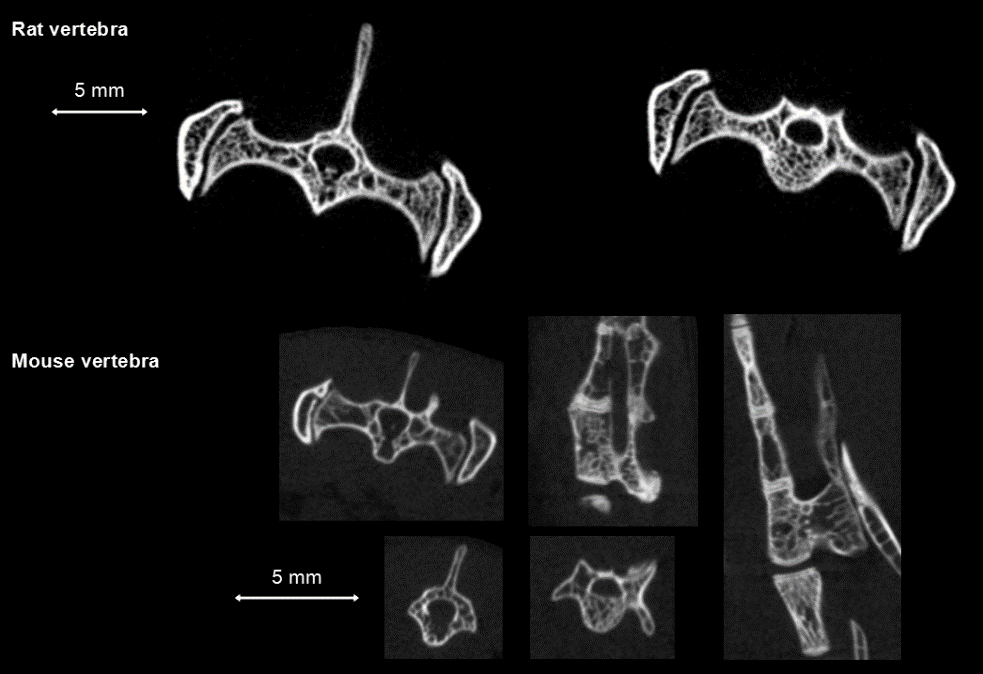

4、骨骼CT成像

骨骼腫瘤研究:大鼠活體CT顯示腫瘤引起腦轉(zhuǎn)移和骨轉(zhuǎn)移,骨骼中產(chǎn)生大量空洞,F(xiàn)DK重建,50μm voxel size。

鼠的尾椎骨活體測(cè)量:高清晰度環(huán)形獲取,獲取時(shí)間:2min3s,ISRA重建,50μm voxel size。

尾椎骨測(cè)量.png

鼠的脊椎骨活體測(cè)量:高清晰度環(huán)形獲取,獲取時(shí)間:4min,F(xiàn)DK重建,50和20μm voxel size。

脊椎骨測(cè)量.png